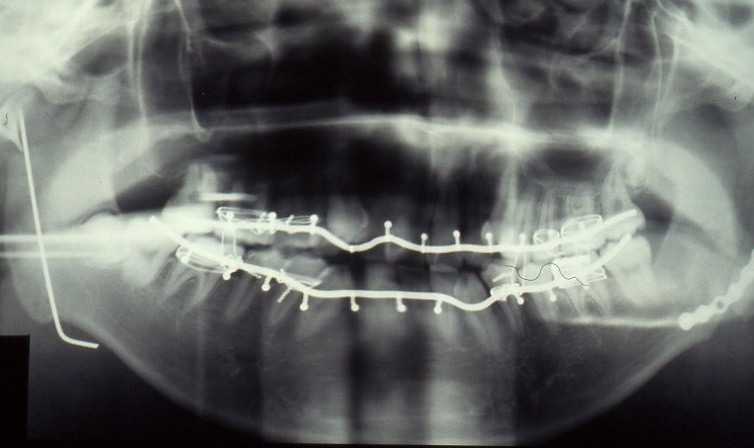

症例2:左下顎角部、右関節頭の骨折

勤務医時代の症例です。

関節頭部はKirchnerワイヤーで固定、

その後顎間固定を行って交互をあわせ、シャンピーのミニプレートで骨の接合を行いました。